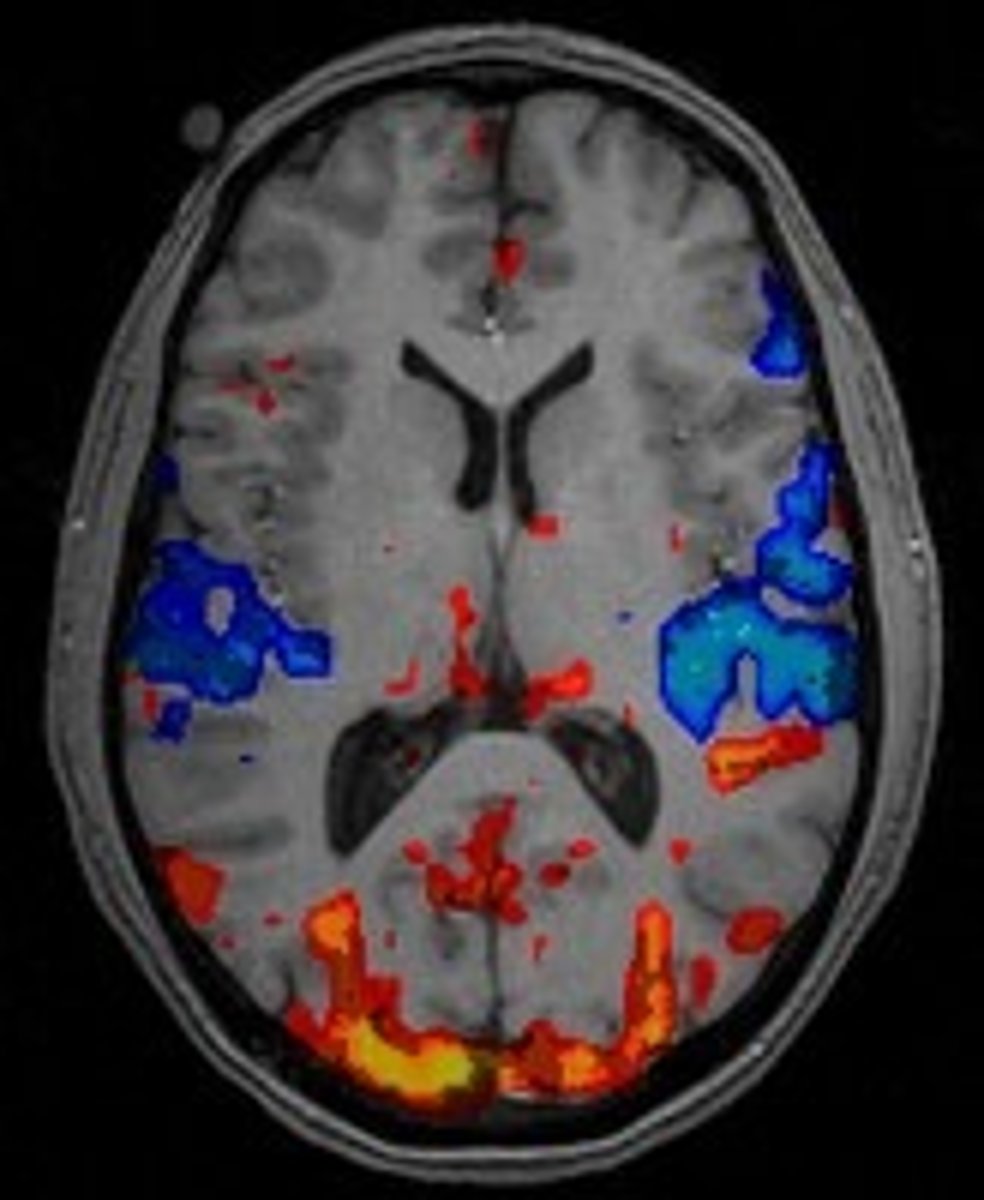

fMRI

knowt flashcard image